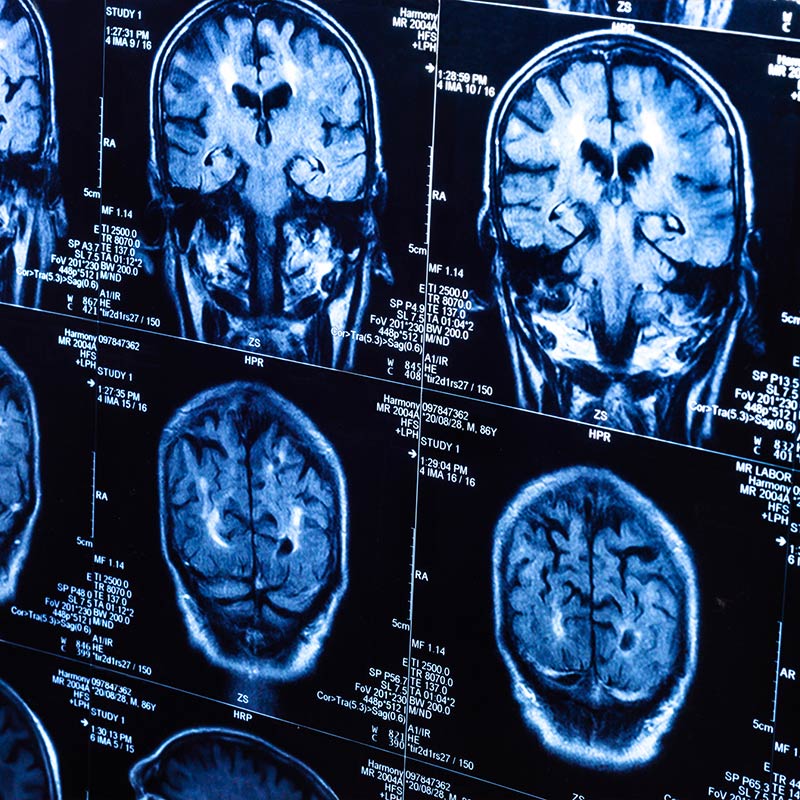

La Unidad Asistencial de Neurología del Centro Médico IMQ Colón tiene como objetivo el estudio, diagnóstico y tratamiento de todas las enfermedades que afectan al Sistema Nervioso Central (cerebro y médula espinal), Periférico (nervios y músculos) y Autónomo (conjunto de nervios que regulan el funcionamiento de vísceras o de funciones automáticas como la respiración, etc).

Trata los trastornos del sistema nervioso. Se ocupa de la prevención, diagnóstico, tratamiento y rehabilitación de todas las enfermedades que involucran al sistema nervioso.

Demencias